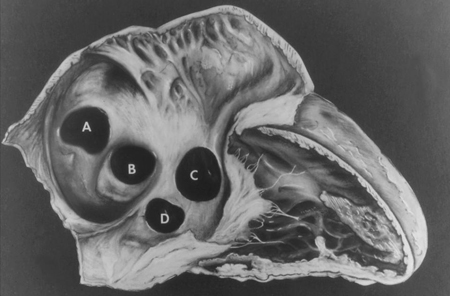

Subtipos de comunicaciones interauriculares: (A) seno venoso; (B) ostium secundum; (C) ostium primum; (D) seno coronario sin techo